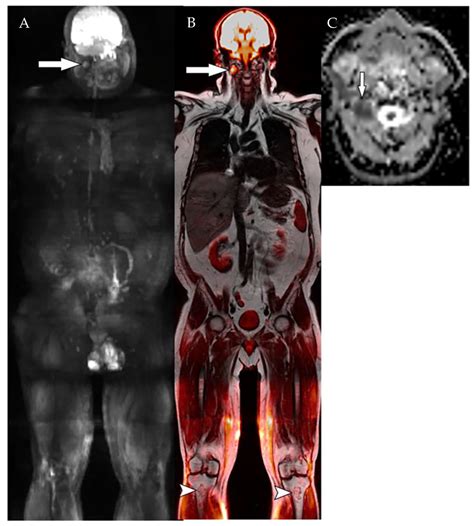

Multiple Myeloma - Symptoms & Causes | MD Anderson Cancer Center